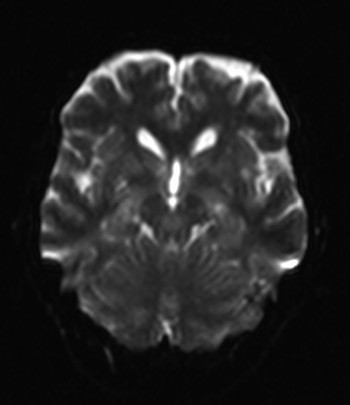

Supplerende undersøkelser med CT caput viste ingen sikre patologiske forhold, men mulig hypodenst område i venstre oksipitalregion. Cerebral MR, inkludert diffusjonsvektede serier, viste små foci med diffusjonsrestriksjon i begge cerebrale og cerebellare hemisfærer (fig 1), som uttrykk for akutte iskemiske lesjoner. CT thorax avkreftet lungeemboli i de store lungekar. D-dimer var > 4,0 mg/l.

Paradoks cerebral embolisme skyldes emboluser til hjernen via åpentstående foramen ovale. Vår pasient hadde ingen anamnese på tromboembolisk sykdom og fikk standard postoperativ antitrombotisk behandling. Pasienten hadde uspesifikke cerebrale symptomer, med forvirring og endret bevissthet. Ved akutt cerebral tromboembolisme dominerer vanligvis fokale nevrologiske utfall symptombildet. Vår pasient hadde feber, takykardi og stigende CRP uten påviselig infeksjonsfokus. Infeksjon i forløpet av akutt hjerneslag er ikke uvanlig, men ses vanligvis etter noen døgn. Embolisme som skyldes platetromber eller fibrinrike tromber gir ikke høy feber eller forhøyet CRP. Feber kan ses ved store hjerneinfarkter uten samtidig infeksjon, på grunn av vevsskaden. Cerebral MR et døgn etter symptomdebut viste hos vår pasient multiple punktformede hyperintense lesjoner i hvit substans i begge hemisfærer.